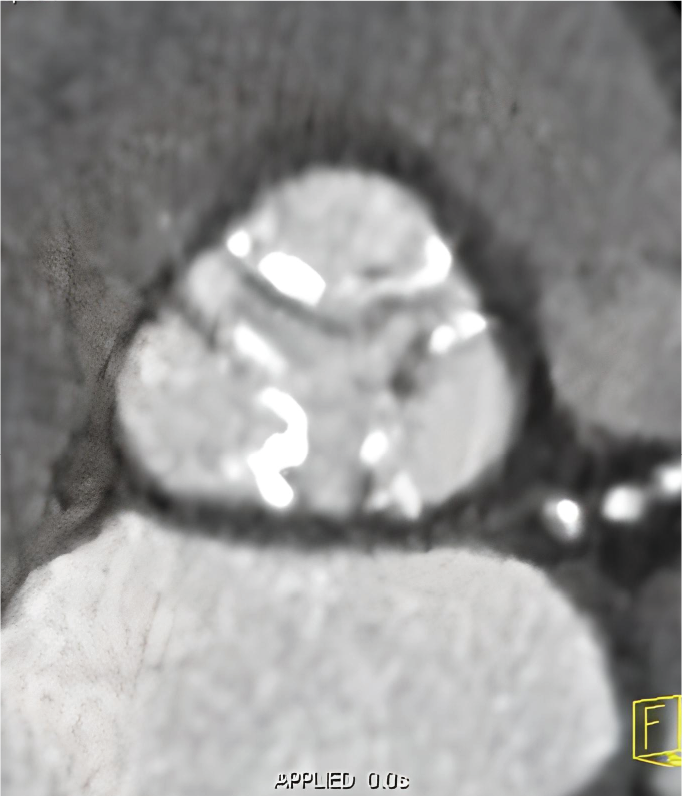

Tomografía cardiaca

Este estudio es adquirido con un tomógrafo de alta velocidad y baja radiación que permite evaluar las arterias coronarias y demostrar la ausencia o la presencia de placas ateromatosas, que son las que ocasionan un infarto (enfermedad arterial coronaria). Mediante la emisión de rayos X es posible obtener imágenes bidimensionales y tridimensionales del exterior y del interior de las arterias coronarias, del corazón y de la función cardiaca.

Cuando es necesario hacer una evaluación mas precisa de tus arterias coronarias la tomografía cardiaca permite, mediante la inyección de contraste por una vena del brazo, estudiar el interior de las arterias y demostrar si existen o no placas que impiden el paso de sangre hacia el corazón, a esta modalidad de la tomografía cardiaca le conocemos como angiotomografía coronaria, que se adquiere en 30 a 60 minutos, y es hoy día el estudio mas confiable para evaluar en forma no invasiva las arterias que nutren al corazón y que cuando se enferman pueden ocasionarte un infarto.